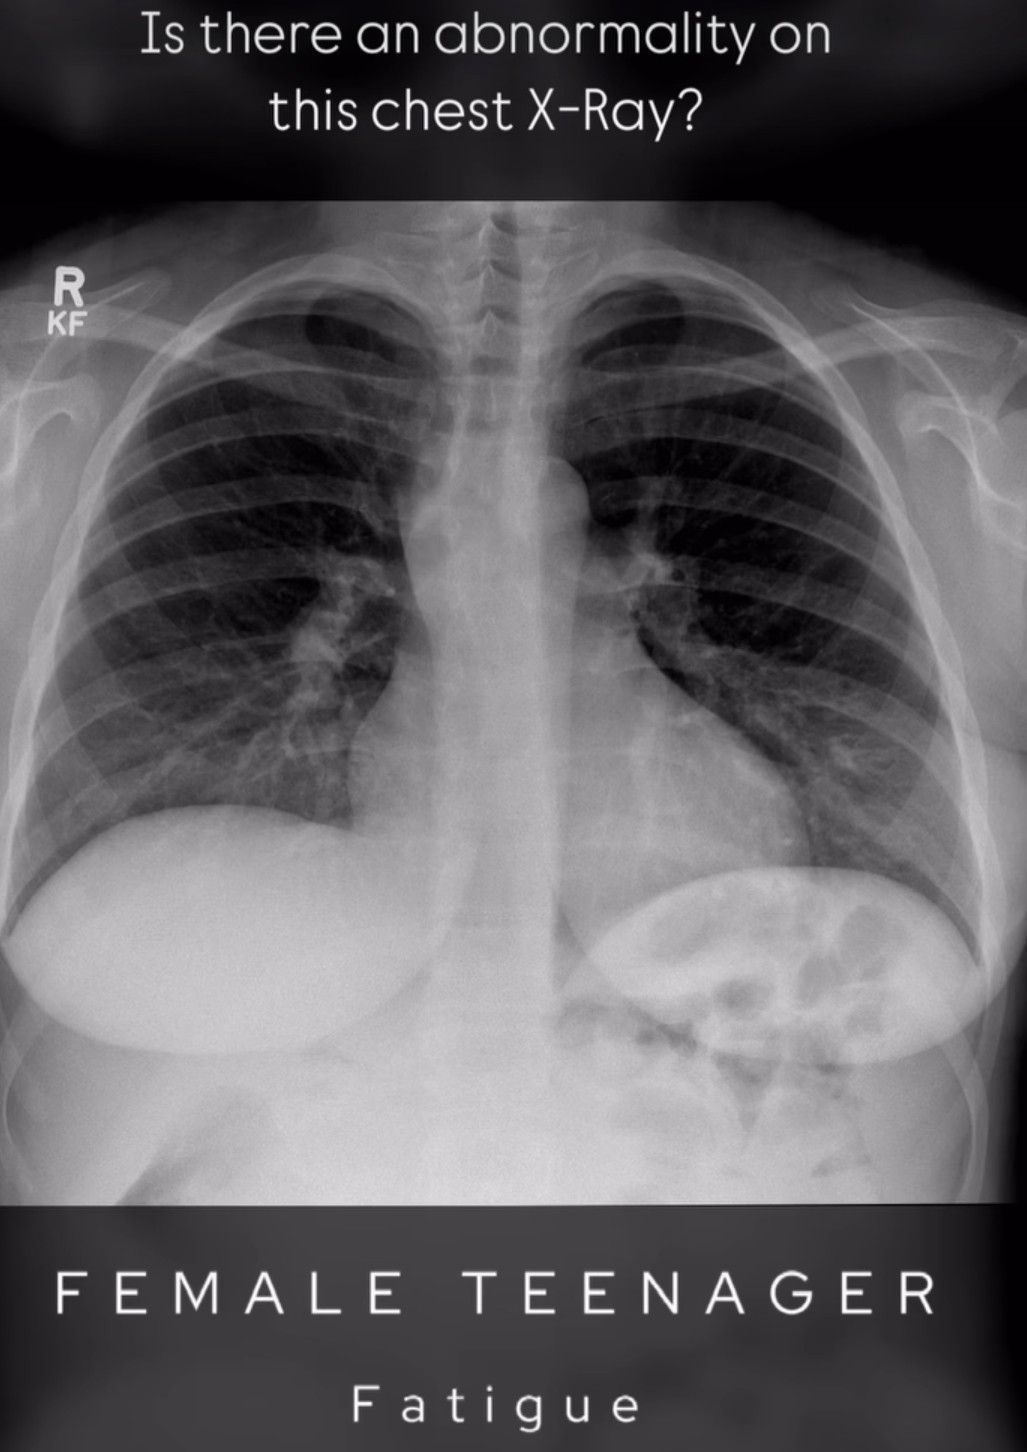

Identify the Abnormality

Identify the abnormality in the picture.